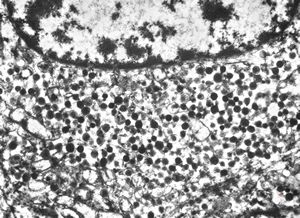

M, 63y. | suprarenal neuroblastoma

M, 3y. | suprarenal neuroblastoma